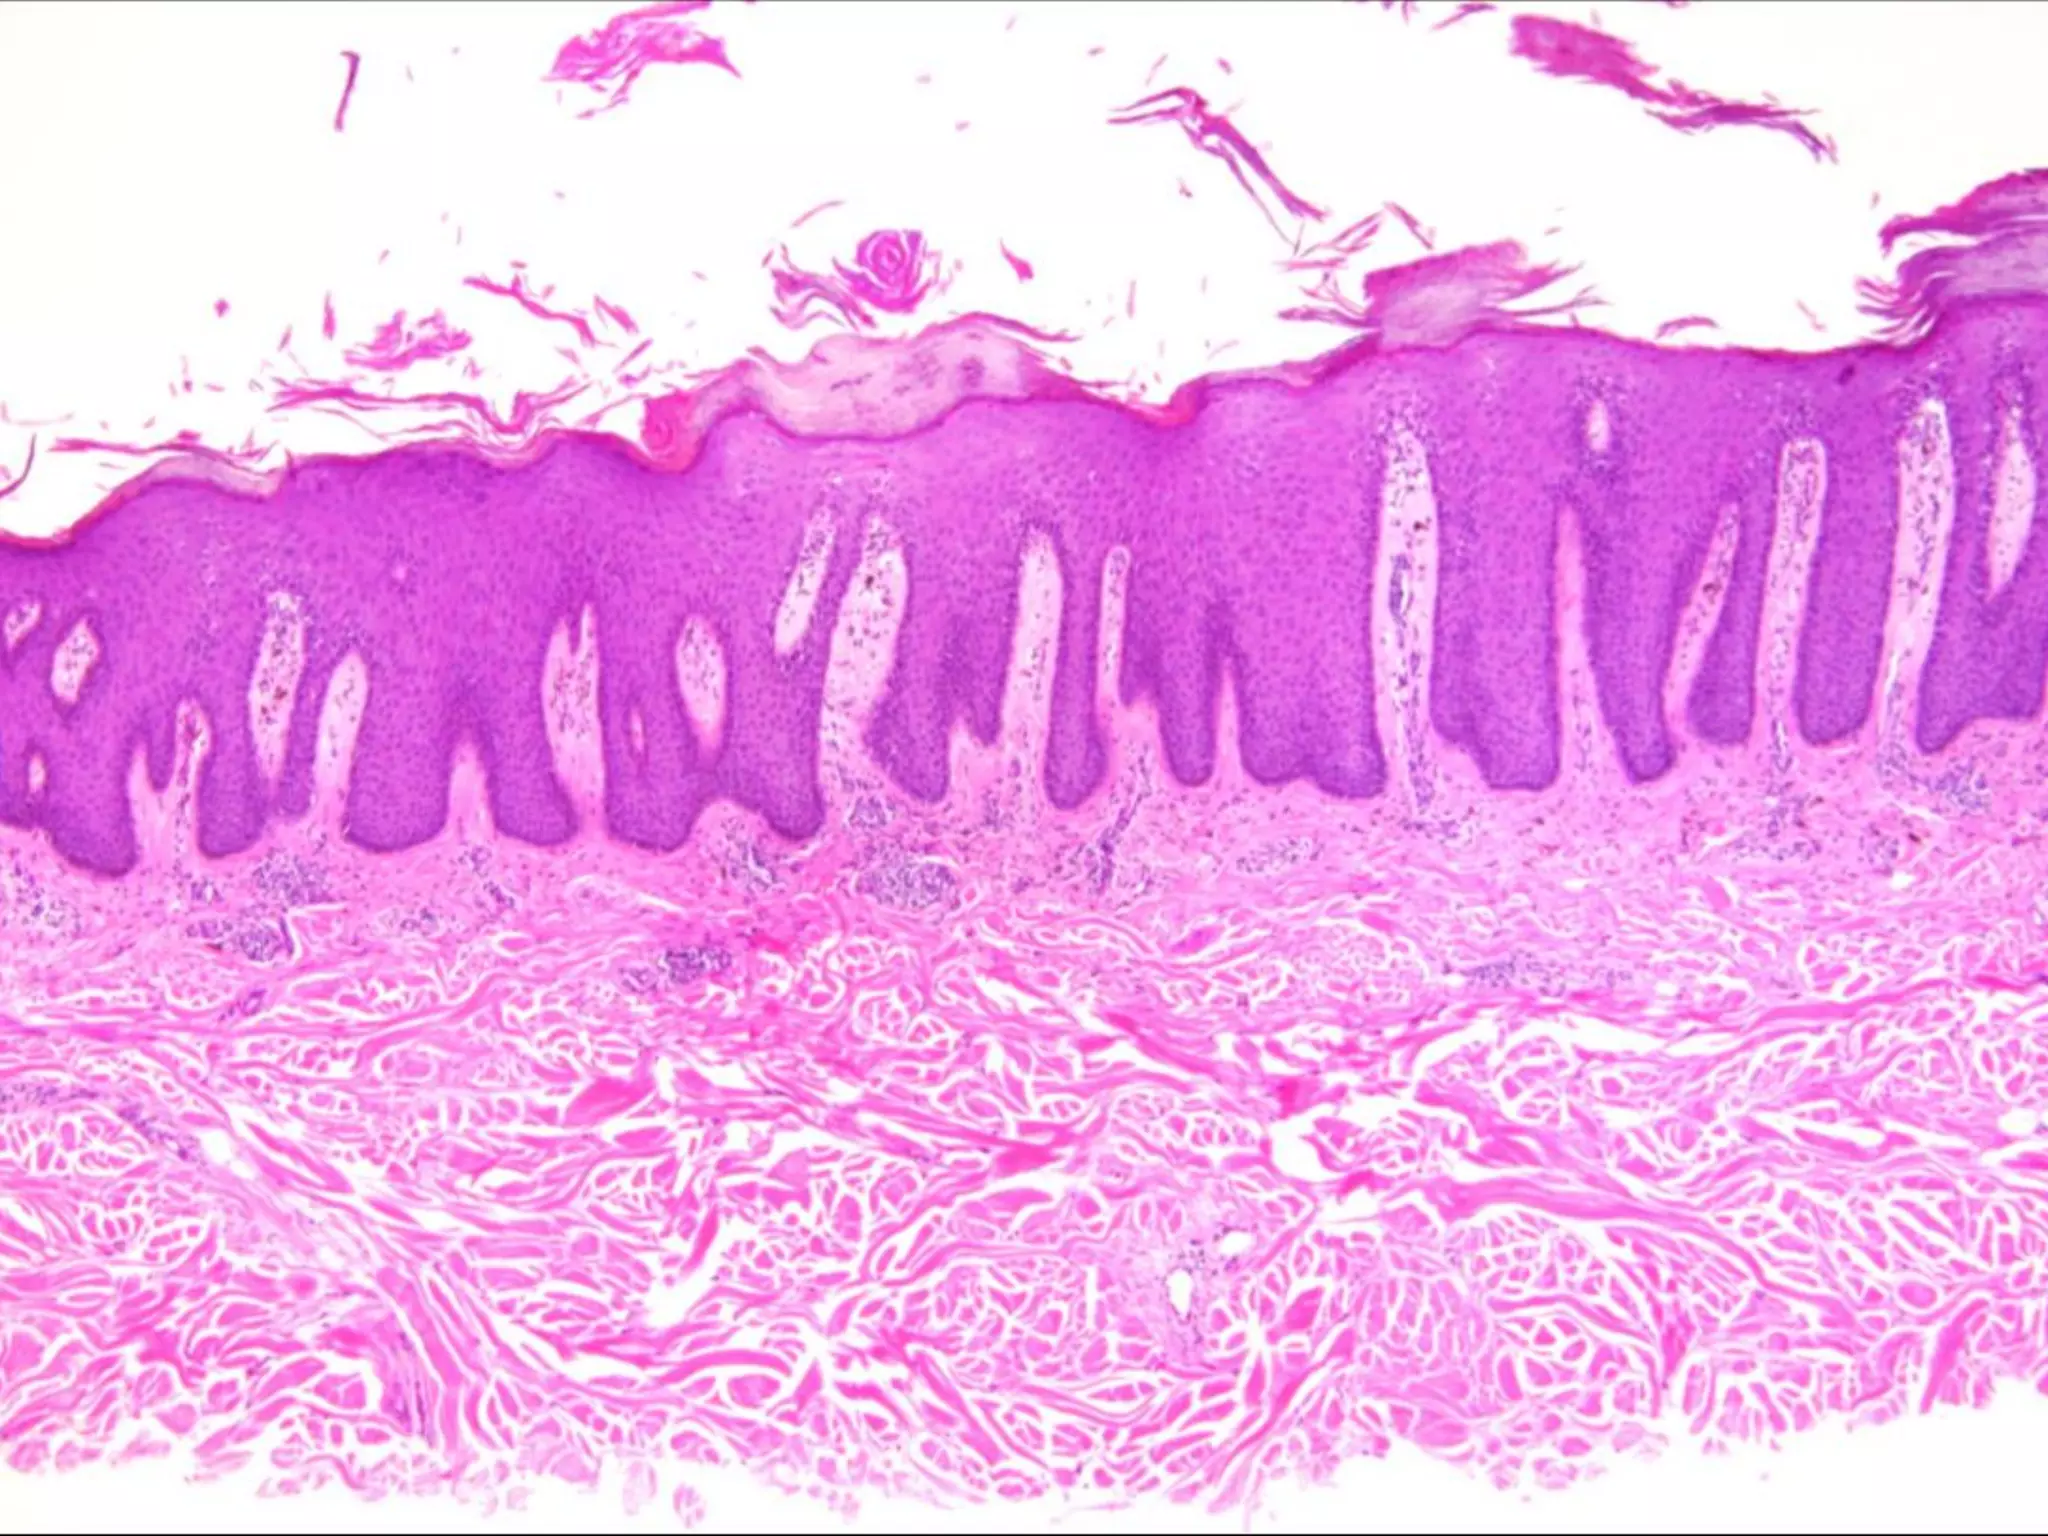

The document provides an overview of dermatopathology, including methods and techniques for skin biopsies such as shave, punch, and ellipse methods. It discusses key terms associated with dermatopathology, such as acantholysis and granulation tissue. Additionally, it references presentations by professionals in the field and essential dermatology resources.